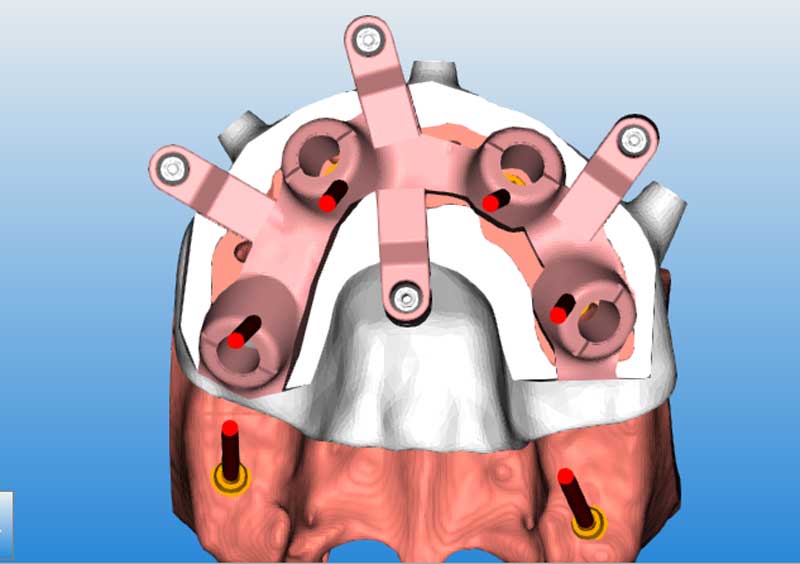

Modellazione 3D della guida chirurgica scomposta

Guida chirurgica primaria su modello stereotipato, la guida è realizzata in titanio e colorata tramite tecnica di anodizzazione

Parte secondaria della guida chirurgica, che si lega alla prima tramite dei mua montati per questo scopo

Provvisorio, che è rapportato alla guida chirurgica per un correto riporto dal progetto al cavo orale